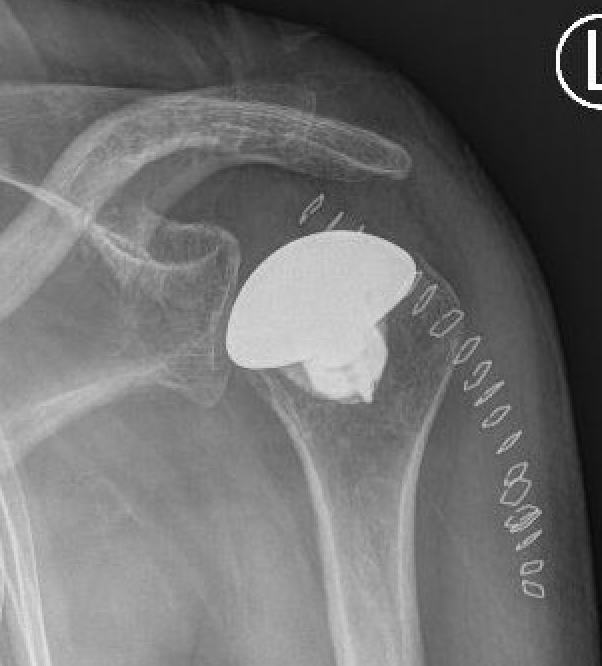

Augmented glenoids

Posterior-wedged augment Stepped augment Full wedged augment

Advantages

- good version correction

- preserves bone stock

- CT evaluation of standard glenoid v posterior stepped augmented glenoid

- posterior stepped glenoid better at correcting version in type B2 and B3

- difficult to restore ML joint line position with both with central glenoid erosion i.e. type A2 or B3

Sheth et al. Should Elbow 2022

- systematic review of augmented glenoid components

- 9 studies and 312 patients

- increased radiolucency seen with 16 wedges and 5 mm steps